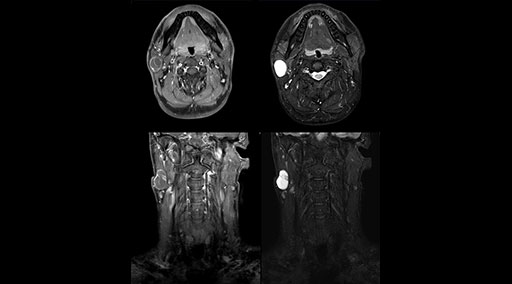

mDIXON TSE fat suppression helps DMG reduce repeats and supports diagnostic confidence

“Our DMG Lisle location includes a cancer center, so soft tissue neck scans, brachial plexus scans, and prostate scans are common. For these exams, mDIXON TSE provides excellent images with and without fat suppression all while helping us reduce repeats and work more efficiently,” Mr. Duffy says.

“With the 2-echo Philips mDIXON TSE the timing is short and the fatsat is very robust. The biggest thing is that you know your fat suppression will be good, even in thin patients or large patients that are off-center,” Mr. Sybesma says.

“Since we work in fixed time slots, not having to repeat scans is key for us,” Mr. Duffy adds. “With mDIXON TSE we get high quality results the first time – unless of course the patient absolutely jumps off the table. For us, that’s significant, because just a single repeat scan could put us behind schedule.

“mDIXON TSE raises our diagnostic confidence with its homogeneous

fat suppression. Neck exams and rheumatology patients are two examples where mDIXON TSE is especially useful,” Dr. Kaakaji says. “For us it’s also an efficiency boost in exams where we need pre and post T1-weighted images with great fat suppression.”

“mDIXON TSE raises our diagnostic confidence with its homogeneous fat suppression”